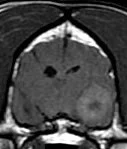

When to Refer and CT or MRI?

We will be discussing how to assess patients with neurological signs and what to consider when deciding whether to manage conservatively or whether to refer for further investigation and treatment. We will also consider the relative merits and disadvantages of both CT and MRI for imaging in neurology with the help of case studies.